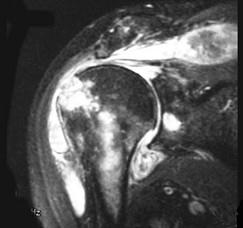

问题 女,71岁,有多年的系统性红斑狼疮病史,高剂量的类固醇服用史,左肩痛,请结合图像,选出最可能的诊断 ( )

选项 A、肱骨头缺血坏死 B、肩关节结核 C、类风湿关节炎 D、骨纤维肉瘤 E、化脓性关节炎

答案 B